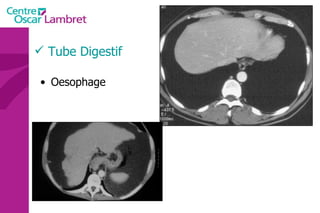

L’Œsophage  : C’est un conduit qui fait communiquer le pharynx en haut et l'estomac en bas. Il mesure environ 25 cm et a un diamètre de 2 à 3 cm. Tube Digestif

L’Œsophage  : On lui décrit quatre portions. Une partie cervicale :  à la base du cou(C6) et en arrière de la trachée. Une partie thoracique : en rapport avec l’aorte thoracique, le canal thoracique, le cœur, les nerfs pneumogastriques et les pédicules pulmonaires.  Une partie diaphragmatique : L’œsophage traverse le diaphragme. Une partie abdominale  :Il se jette dans l’estomac par un orifice appelé le cardia. Tube Digestif

Tube Digestif Oesophage